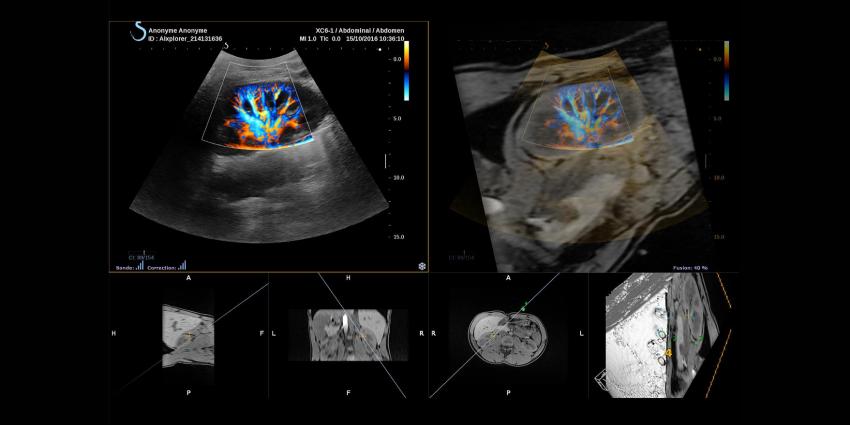

SuperFast application technology by SuperSonic Imagine ensures high image quality. The display mode plays a crucial role in such devices, which is why the image obtained has to be clear and uniform. Tissue Tuner technology can adapt the ultrasound speed for multiple organs, which creates more possibilities for the doctors in different situations.

- Angio PL.U.S – takes microvascular visualization to a new level with the help of improved color sensitivity technology;

- TriVu – a unique ultrasound system, offering real-time imaging, combining B-mode, SWE™ and Color+ imaging. Due to this, anatomy, tissue stiffness and vessels can be visualized simultaneously.